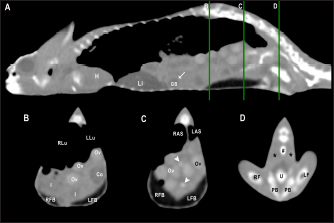

Fig. 4. Sagittal precontrast CT image displayed in soft tissue window (A) and transverse cross-sectional views of gross anatomical sections at the level of the liver (B), gallbladder (C), fat bodies (D), and kidneys (E) in a veiled chameleon (C. calyptratus). The right of the patient is on the left of the image. H, heart; RLu, right lung; LLu, left lung; Es, Esophagus; RLi, right liver lobe; LLi, left liver lobe; ST, stomach; GB, gallbladder; RK, right kidney; LK, left kidney; RT, right testicle; LT, left testicle; RFB, right fat body; LFB, left fat body; Co, colon.

Heart, liver, including caudal vena cava (CVC), hepatic vessels, and gallbladder, esophagus, stomach, intestines, cloaca, gonads, fat bodies, kidneys, and when distended, urinary bladder were identified in the CT images with the aid of the anatomical sections (Fig. 4). The spleen, pancreas, and adrenal glands could not be identified. Measurement values of the liver, testes, fat bodies, and kidneys observed in CT in veiled and panther chameleons are seen in Table 1.

In the present study, all soft-tissue window transverse images were compared with their corresponding anatomical slice. The sectional anatomy of the coelomic organs in veiled and panther chameleons allows a correct morphologic and topographic evaluation of the anatomic structures, which is a useful tool for the interpretation of the CT images.